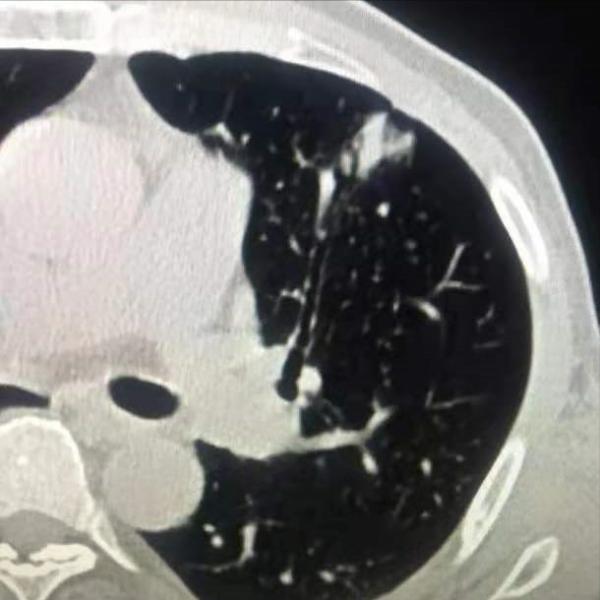

肺腺癌是肺癌的一種,屬於非小細胞肺癌。一般起源於支氣管粘膜上皮,少數起源於大支氣管的粘液腺。腺癌細胞不規則、核仁明顯、胞漿豐富、常含黏液,是肺癌中最常見的型別。由於大多數腺癌起源於較小的支氣管,一般病灶處於肺周邊,為周圍型肺癌。早期一般沒有明顯的臨床症狀,往往在胸部CT檢查時被發現,表現為類圓形或橢圓形腫塊。

一般肺鱗癌多發生於老年長期吸菸者,病灶靠近肺門及縱隔,可以在區域性緩慢生長到巨大的腫塊,轉移速度慢,一旦發生轉移,也以淋巴道轉移為主,到較晚期才可能發生血行轉移。而不同於鱗狀細胞肺癌,肺腺癌較容易發生於女性及不抽菸者,肺腺癌長在外周,容易發生經血液迴圈的轉移。